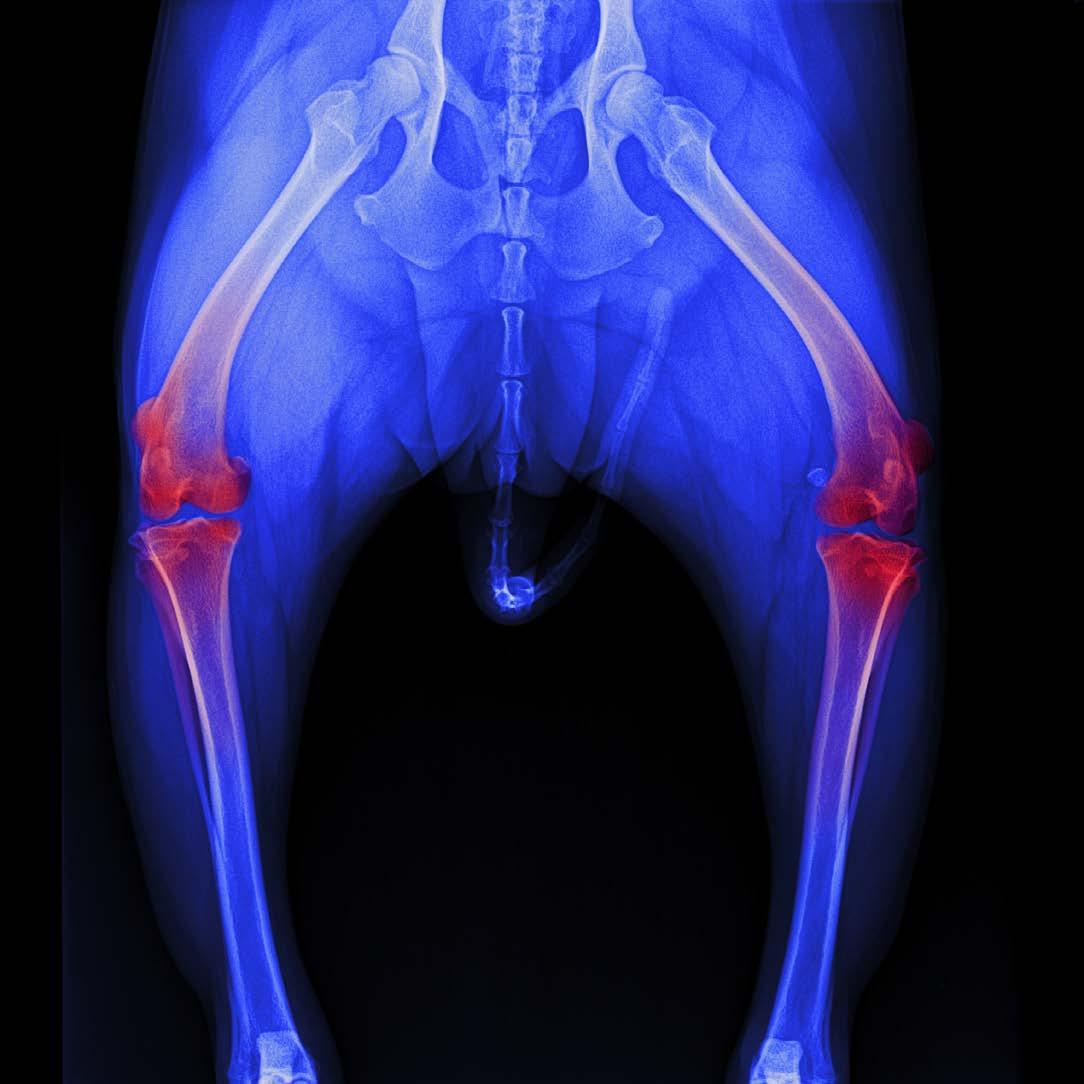

Osteoarthritis (OA) is one of the most common chronic conditions in dogs, and one of the most misunderstood. Many owners attribute stiffness, slowing down or irritability to ‘just getting old,’ when in reality these are signs of pain. Until recently, canine OA treatment options focused mainly on nonsteroidal anti-inflammatory drugs (NSAIDs), joint supplements, weight management and physiotherapy.

But the release of Librella®️ (bedinvetmab) has introduced an entirely new class of pain relief: one that is long-acting, targeted, and specifically designed for chronic arthritis in dogs. If your dog has OA or is showing early signs, this medication may be part of the future of comfort-focused care.

Your vet may recommend it if your dog:

• Shows stiffness after resting

• Becomes reluctant to jump into the car or onto furniture

• Slows down on walks

• Has difficulty standing up

• Becomes grumpy when touched

• Shows lameness that comes and goes

Earlier intervention leads to better outcomes, and many vets are now using Librella®️ as part of multimodal pain management, even in early OA.

My dog looks stiff after resting; is it arthritis?

Stiffness after rest, especially when rising from sleep, is one of the earliest and most common signs of canine osteoarthritis, particularly in middle-aged and senior dogs.

SIGNS SUGGESTING ARTHRITIS

• Slow to stand after lying down

• Hesitation on stairs or jumping into cars

• ‘Bunny hopping’ or altered gait

• Less interest in long walks

• Stiffness that improves as they ‘warm up’

• Irritability when touched over hips, back or elbows

OTHER CONDITIONS THAT MIMIC ARTHRITIS

• Muscle strain

• Cruciate ligament disease

• Neurological weakness

• Hip or elbow dysplasia

• Lyme disease or immune-mediated joint disease

A vet exam and possibly X-rays are the best way to confirm.